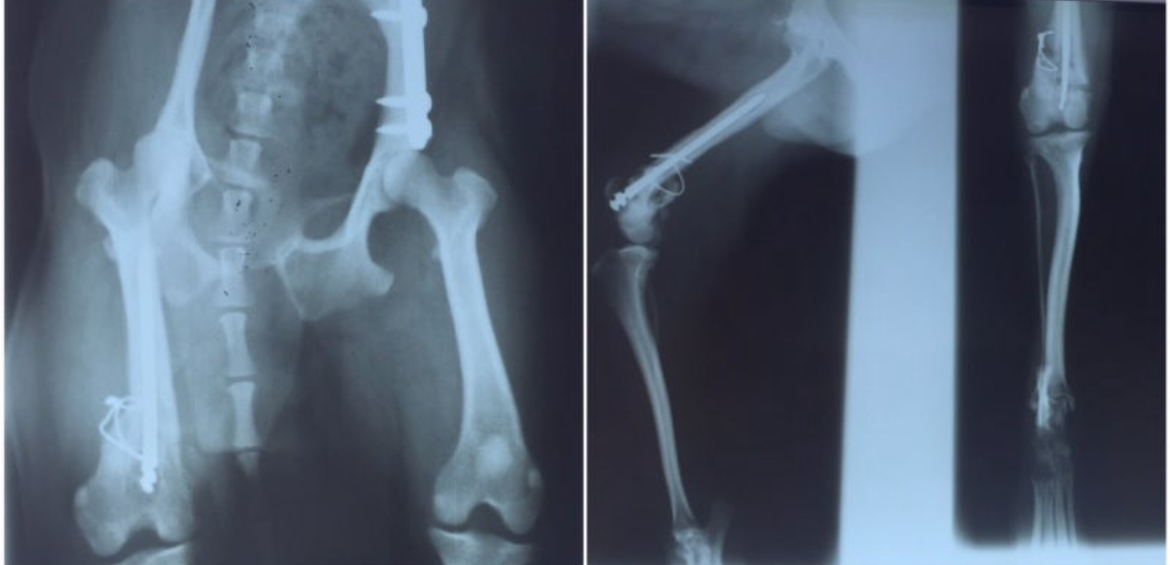

엑스레이 속 뼈는 얼기설기 이어져 있었다.

철사는 살을 찔렀고,

굳은 피가 근육과 엉켜 있었다.

수의사는 중얼거렸다.

“시대가 어떤 시댄데 이런 수술을…”

또랑이 뒷다리 둘다 교통사고(?) 후 골절 상태, 시골 병원에서 대충 얼기설기 철사로 묶어놓은 모습

세 번째, 그리고 네 번째 수술.

그는 네 번의 칼을 견뎠다.

오른쪽 뒷다리는 끝내 굽지 않았다.

앉을 때마다 그 다리를 쭉 편 채 있었다.